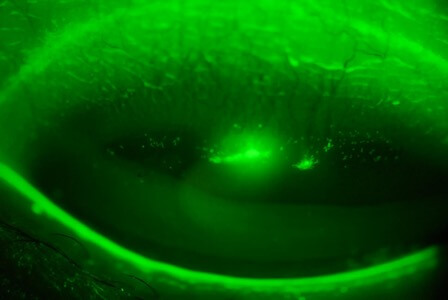

乾眼

市民選購隱形眼鏡時,可能經常聽到含水量這個名詞,有部份人甚至誤信鏡片含水量越高就越舒服這個說法,實情卻是鏡片含水量越高,配戴者越容易引發眼乾這個併發症。角膜比您的皮膚更需要水份滋潤,平時淚水會以一層薄膜覆蓋眼球表面,淚水不足,眼睛自然感到乾澀、痕癢。隱形眼鏡屬於外來物,少不免會影響淚膜的穩定性,加速其自身的揮發速度,所以很多隱形眼鏡配戴者都會受到乾眼症的困擾。乾眼症患者大多會選用人工淚液去緩解症狀,但這只能治標,要避免問題惡化,就先要找出問題根源,再對症下藥,例如更換更保濕的隱形眼鏡、縮短配戴時間、又或停用隱形眼鏡等等,方法各有不同。

乾眼

照片由香港理工大學眼科視光學院提供